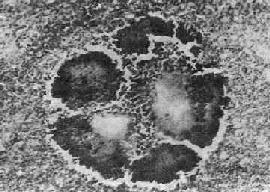

图18-32 脑隐球菌病

切片示脑组织内形成许多小囊腔,腔内充满隐球菌及其所分泌的凝胶样物质